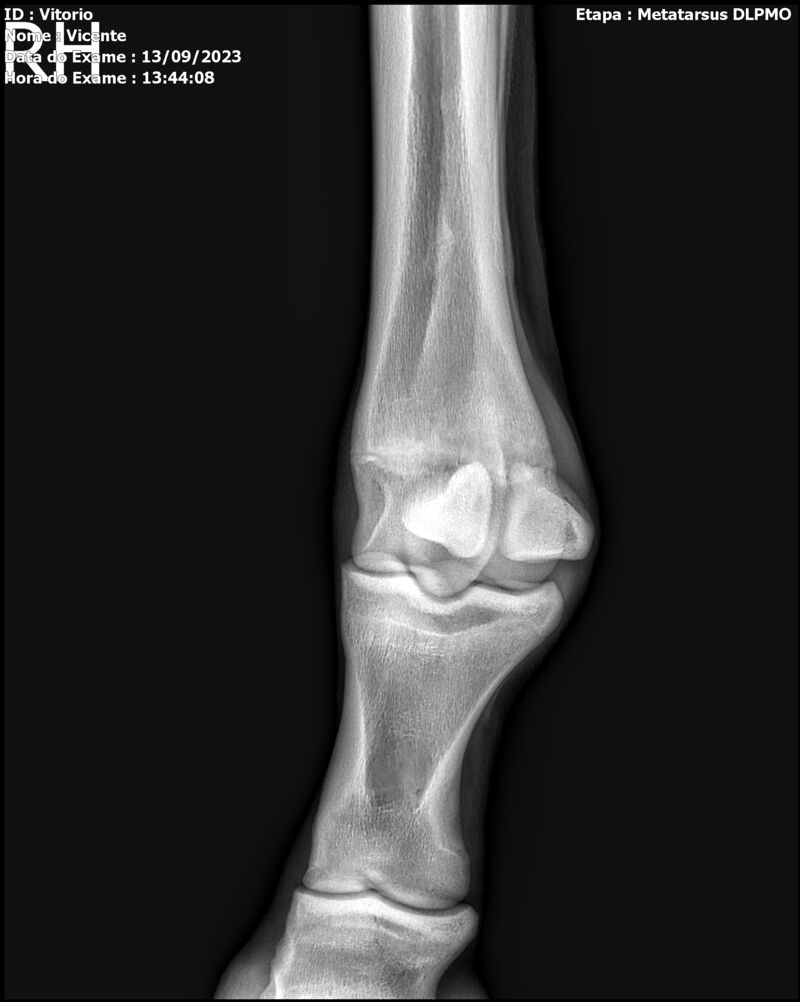

LOTE 13

THUNDER ZC

Raça: BRASILEIRO DE HIPISMO

Sexo: MACHO - POTRO

Nascimento: 17/09/2022

Altura Aproximada: 1,54

Pel.: CASTANHO

Registro: EM AND

Vend.: VICENTE CONTE

Local : PORTO FELIZ/SP